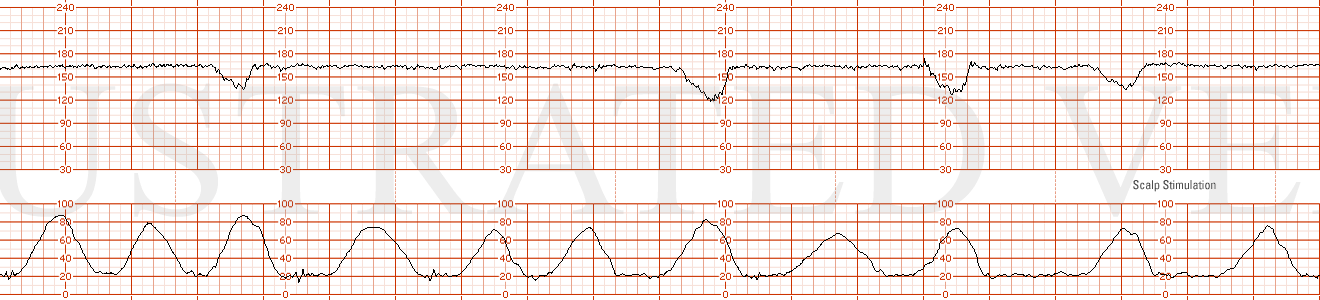

STRIP 76

1. Ctxs – 11 contractions each 50 sec 55 sec 50 sec, etc duration (3rd contraction from end too long)

Baseline -140bpm with mod variability -7-8 bpm

Decels - None

Accels – None until scalp stimulation to be written on strip done at 14 min into strip – 18 bpm x 20 sec

Ctxs2 – 10 contractions – each 60, 65, 60, 65 etc sec duration.

Baseline2 – 150 bpm with mod variability 7-8 bpm

Decels2 - Late Decel with Ctx 2, Ctx 8 (more gradual, less variable looking), each 15 bpm nadir

Variability2 – moderate at 7-8 bpm

Accels2 – none scalp stim not done.